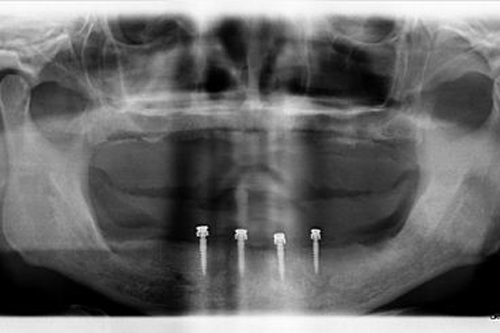

dental implant xray

The consultation usually begins with a review of your medical and dental history, followed by a thorough oral examination. This may include X-rays or 3D imaging to assess your bone structure and determine if Pterygoid Dental Implants are suitable for you.